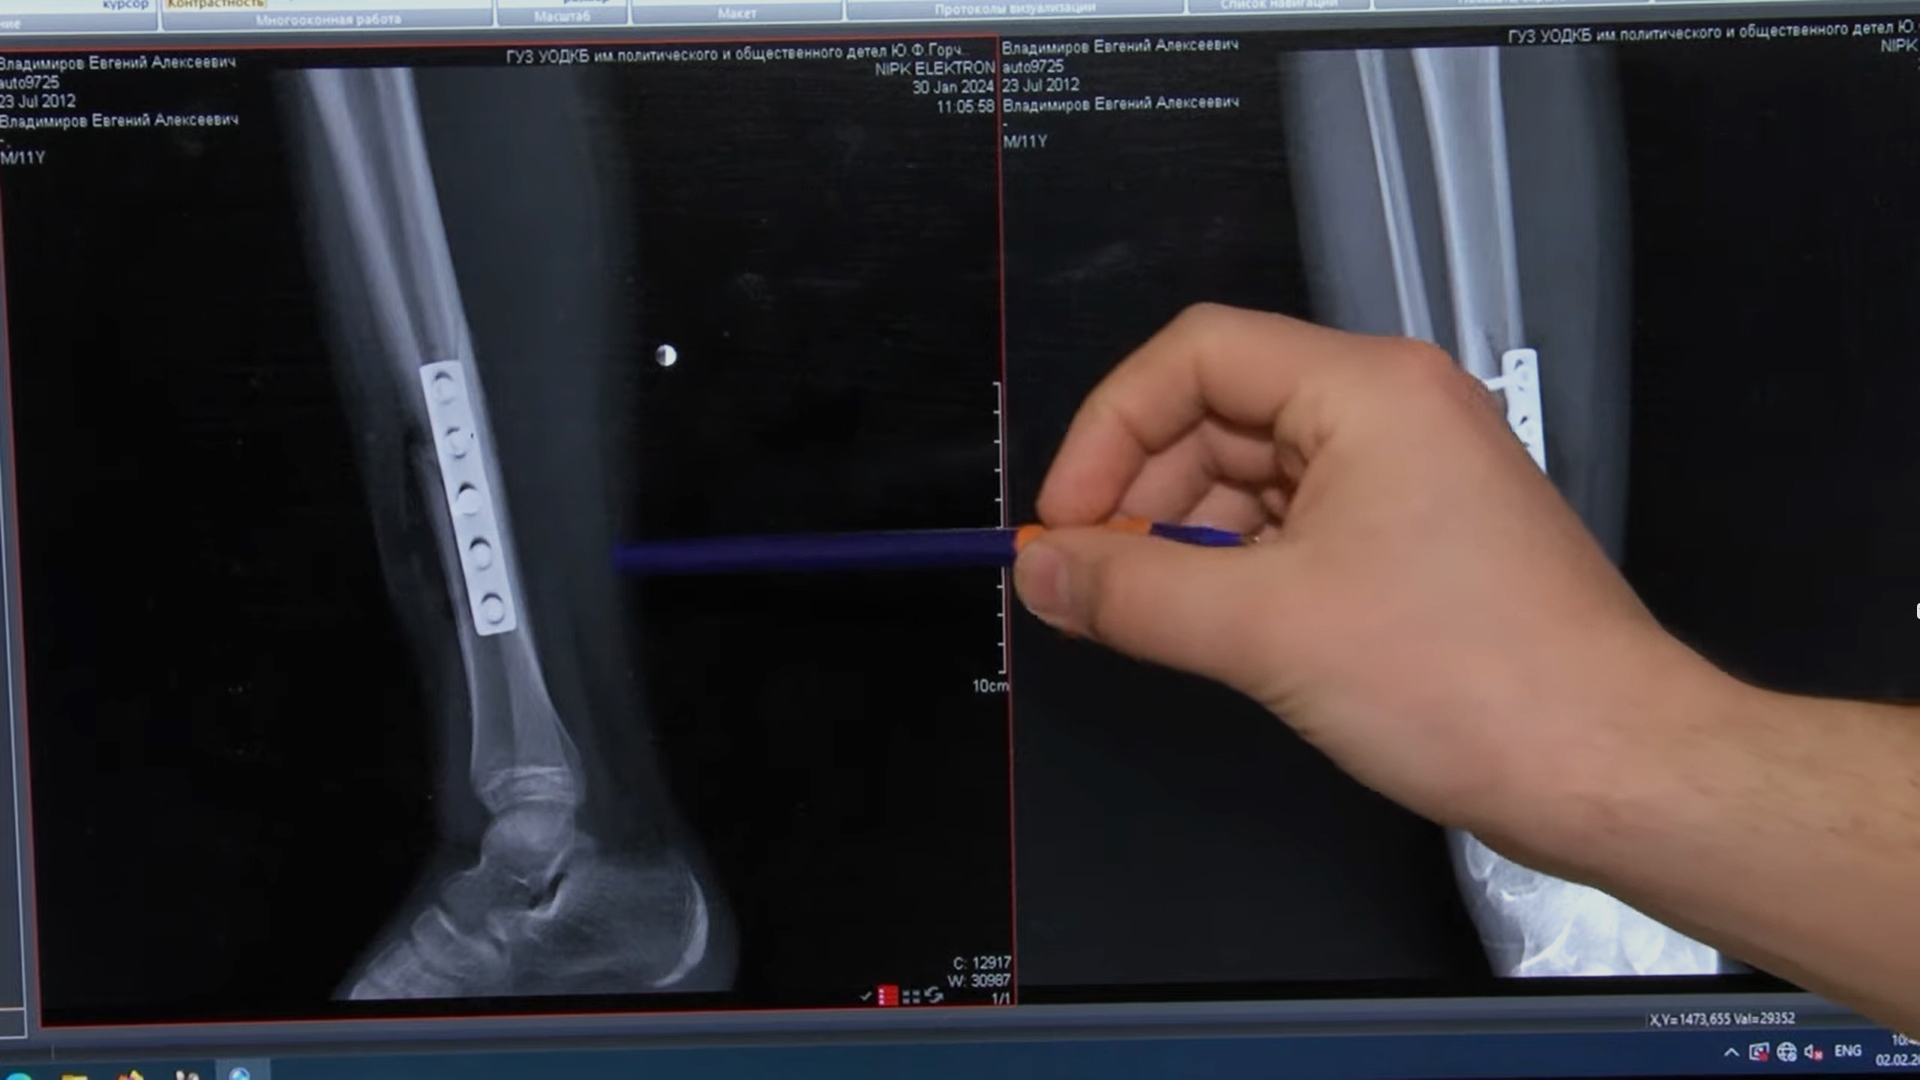

— Эпидемия травматизма. О том, что зимой падает снег, и кто падает на снег.